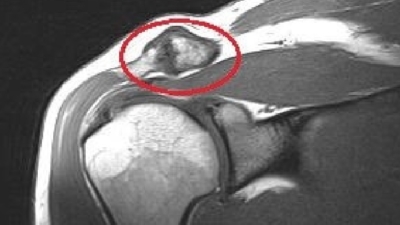

Wanneer is een MRI nodig?

Bij AC gewricht klachten is een MRI zelden het eerste onderzoek.

Echo en röntgen geven bij de meeste patiënten voldoende informatie.

Een MRI kan wel aanvullend zijn wanneer:

Als er twijfel blijft over de oorzaak van de klachten ondanks echo en röntgen. We een peesscheur vermoeden die mogelijk geopereerd moet worden.

Er sprake is van botoedeem in het sleutelbeen of het schouderdak — een teken van actieve ontsteking dat alleen op MRI zichtbaar is.

De valkuil van MRI bij het AC gewricht

Op een MRI wordt vrijwel altijd artrose in het AC gewricht gerapporteerd. Bij 75% van alle mensen boven de 40 — en bij 100% boven de 70 — toont de MRI tekenen van slijtage. Het risico is dat dit als de oorzaak van uw pijn wordt gezien, terwijl het een toevalsbevinding is.

AC gewricht artrose MRI

Onderzoekers adviseren daarom om MRI-bevindingen van AC artrose te beschrijven als “leeftijdsgebonden veranderingen” en de diagnose niet alleen op beeldvorming te baseren.

💡 Ons advies: Een MRI vragen we pas aan als echo en röntgen geen duidelijk beeld geven, of als we vermoeden dat er meer aan de hand is dan alleen het AC gewricht. In de meeste gevallen is een MRI bij AC klachten niet nodig.